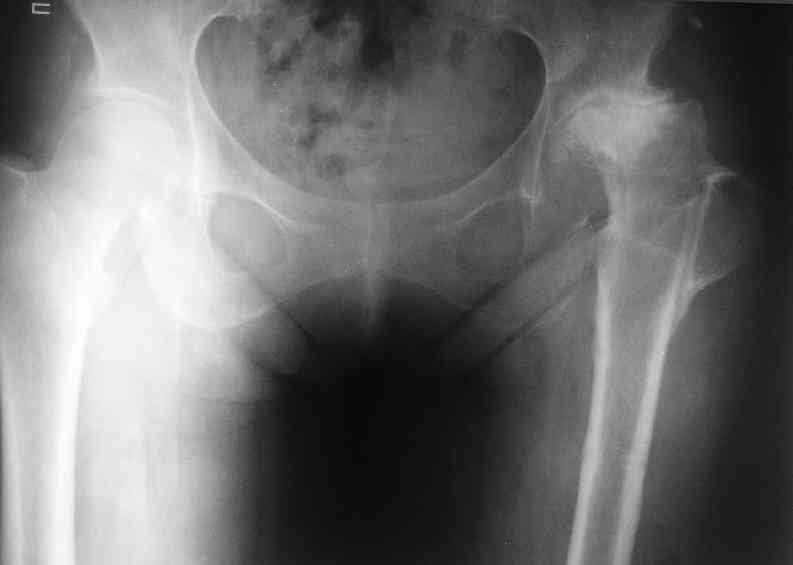

А нельзя показать снимок таза с контралатеральным суставом.

AV> опираясь на стул. На ногу не наступает. Укорочение 8 см. Иногда

А за счет чего такое укорочение? По снимку не видно соответствующего дефекта. Ну плюс приводящая контрактура - но все равно как-то уж больно много. Может, сделать снимки и таза обзорный с обоими проксимальными отделами бедра, и коенный суставов с приложенной линейкой какой?

Невозможно не согласиться с Анатолием, чтобы заниматься адекватным планированием как минимум прямая проекция таза должна быть сделана, как

The X ray that you provided does not show 8 cm of shortening. Perhaps you could send one showing the whole pelvis and proximal femurs.

I agree with Dr Eid's comments. The origin of the 8 cm leg length difference is a puzzle. Is this a clinical measurement? In that case contracture of the joint might affect the measurement. Can we see an AP pelvis to include both hip joints (including a calibration object with a known length) so that the difference in leg lengths that can be ascribed to the hip deformity and bony reabsorption can be measured. This sort of xray will help with templating for the TJR also. I would be very tempted to do a one stage procedure and accept some shortening. Shoe lifts should take care of a 3-4 cm difference.

До травмы проблем с ногой не было. Укорочения, болей и т.п. не отмечал. Сегодня перемерял укорочение - меньше 7 см намерять не

получается :)

По уровню малых вертелов (с учетом рентгеновского увеличения) получается 5 см. Клинически ногу низвести путем тракции невозможно. Из движений - сгибание до 40*, остальные движения "символические".